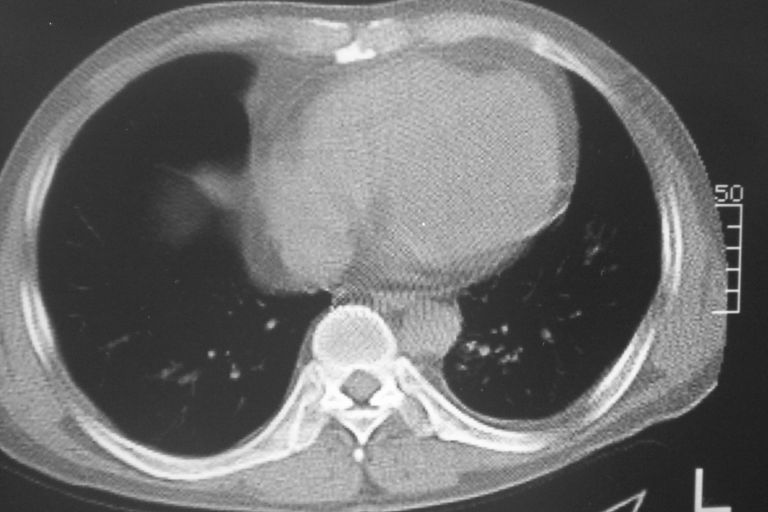

标题: CT10574:男 50岁胸部CT请会诊!

患者 男 50岁 无痛性咯血3天,无其他不适.

1 左肺下叶基底段见两结节软组织密度灶, 肺窗边缘见有毛刺征像, 不能排除占位. 2 建议结合临床治疗一周后ct随访在看其结果.

左下肺基底段两个小结节影,边缘毛糙,建议抗炎治疗后复查。

1 左肺下叶后基底段见结节软组织密度灶,建议抗炎后复查,排除肿瘤

1、左肺下叶两个结节影,建议抗炎治疗后复查.

1 左肺下叶后基底段见结节软组织密度灶,建议抗炎后复查,排除肿瘤。

1 左肺下叶后基底段见结节软组织密度灶,周围见毛刺,建议抗炎后复查,警惕周围型肺癌。